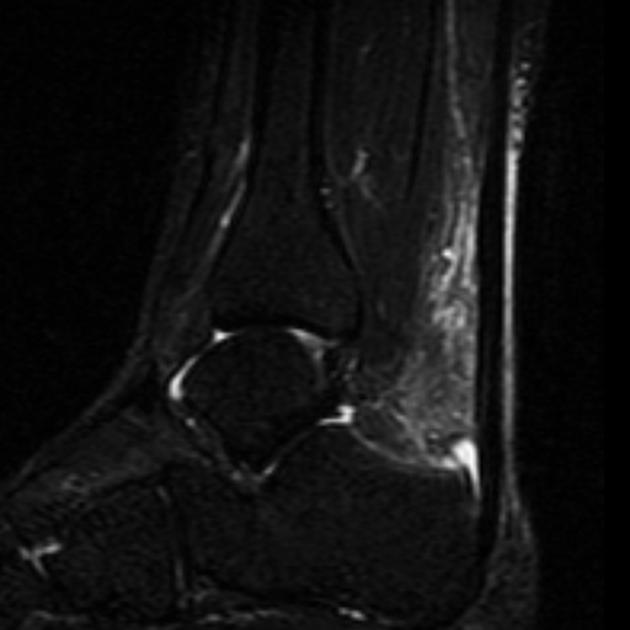

17. 족저근막염과 관련되어 MRI에서 관찰되는 것은 무엇인가?

족저근막염(Plantar fasciitis)은​ 족저골극(plantar enthesophyte)을 가지거나 가지고 있지 않은 족저근막의 근위 부착부에 인접한 곳에서 증가된 T2 신호를 보인다. 근막은 두꺼워질 수 있다. 예후가 불량한 경우는 종골에서 족저근막 부착부 인접 부위의 골수종을 볼 수 있다. (그림 47-3)

△ 그림 47-3. 발목 시상면 STIR 영상. 족저근막염을 가진 환자의 연부조직과 골수종을 보여준다.